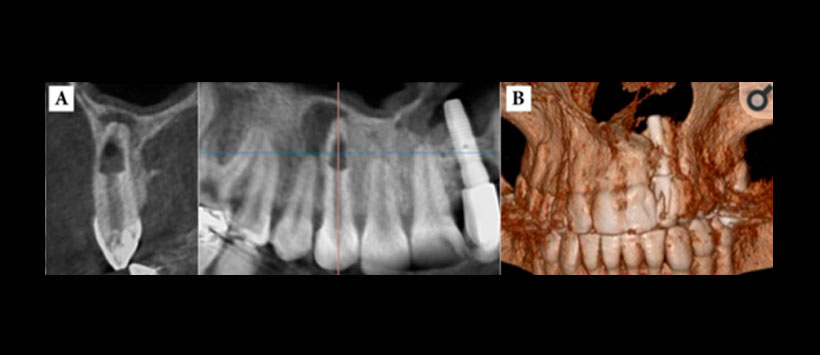

- Evaluacion de zonas de traumatismo alveolodentario – Figura 3